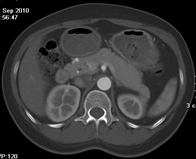

如上圖所示,相鄰的三張軸位圖像未見明顯異常,根據(jù)傳統(tǒng)軸位圖像很難得到準確的臨床診斷。

同一病人利用容積數(shù)據(jù)進行三維處理后,高品質MPR和三維圖像上則清晰顯示了縱向排列的腹腔干與腸系膜上動脈相鄰近,血管發(fā)生變 異,近端血管閉塞,為臨床提供了精確的診斷信息。

從上面的例子可以看到,能否為臨床提供高品質的三維影像成為了16層CT的核心價值,而東芝新一代的 全景三維16層CT擁有最為  先進的3項核心技術,在16層核心價值上的表現(xiàn)自然值得期待。